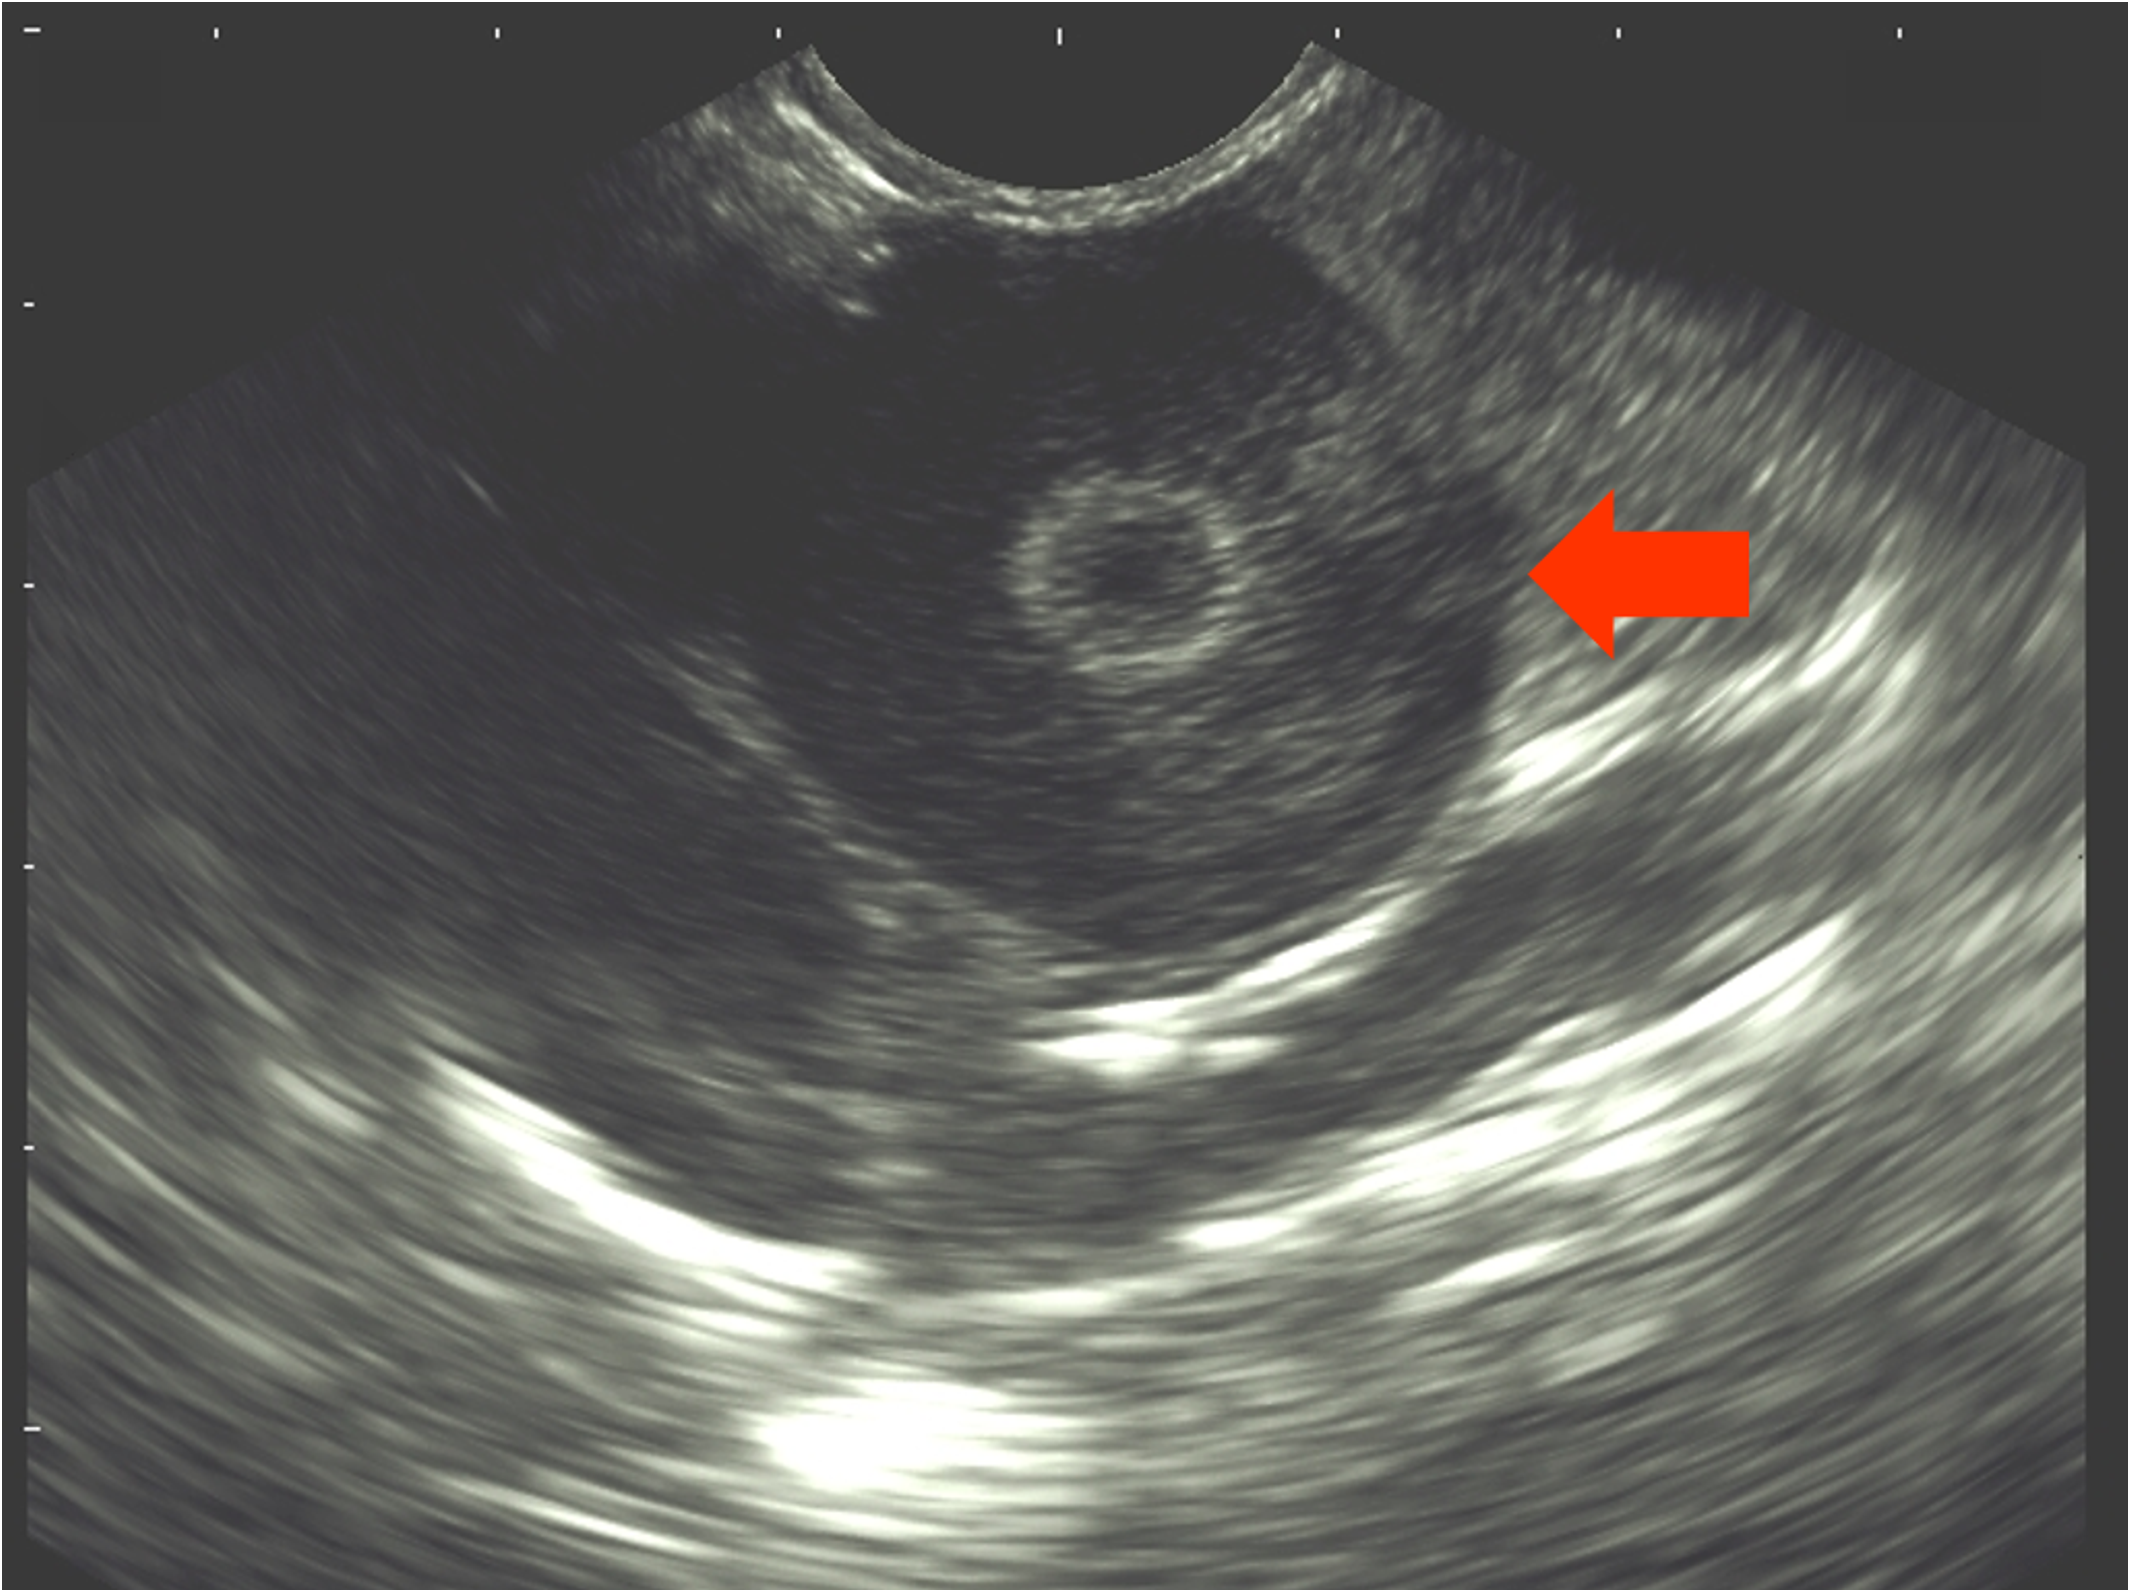

Each hen was examined via ultrasonography weekly (Table 1) to check for ovarian follicles. The examination was conducted with the ultrasound system DUS 60 vet and the microconvex transducer C611-2 (both Edan Instruments GmbH, Shenzhen, China). The transducer was placed on the area between the vertebral column and the caudal rib (Figure 1). A frequency of 9.4 MHz was used and penetration depth varied between 39 and 58 mm. If present, follicles were visible as a round, anechoic zone with a smaller, round, hyperechoic zone in the middle (Figure 2). For each hen, the duration of effectiveness of the implant was assessed based on the number of weeks in which no follicles were detected by ultrasonography.

FIGURE 2

Sonogram of the ovary of a hen. The arrow marks an ovarian follicle.